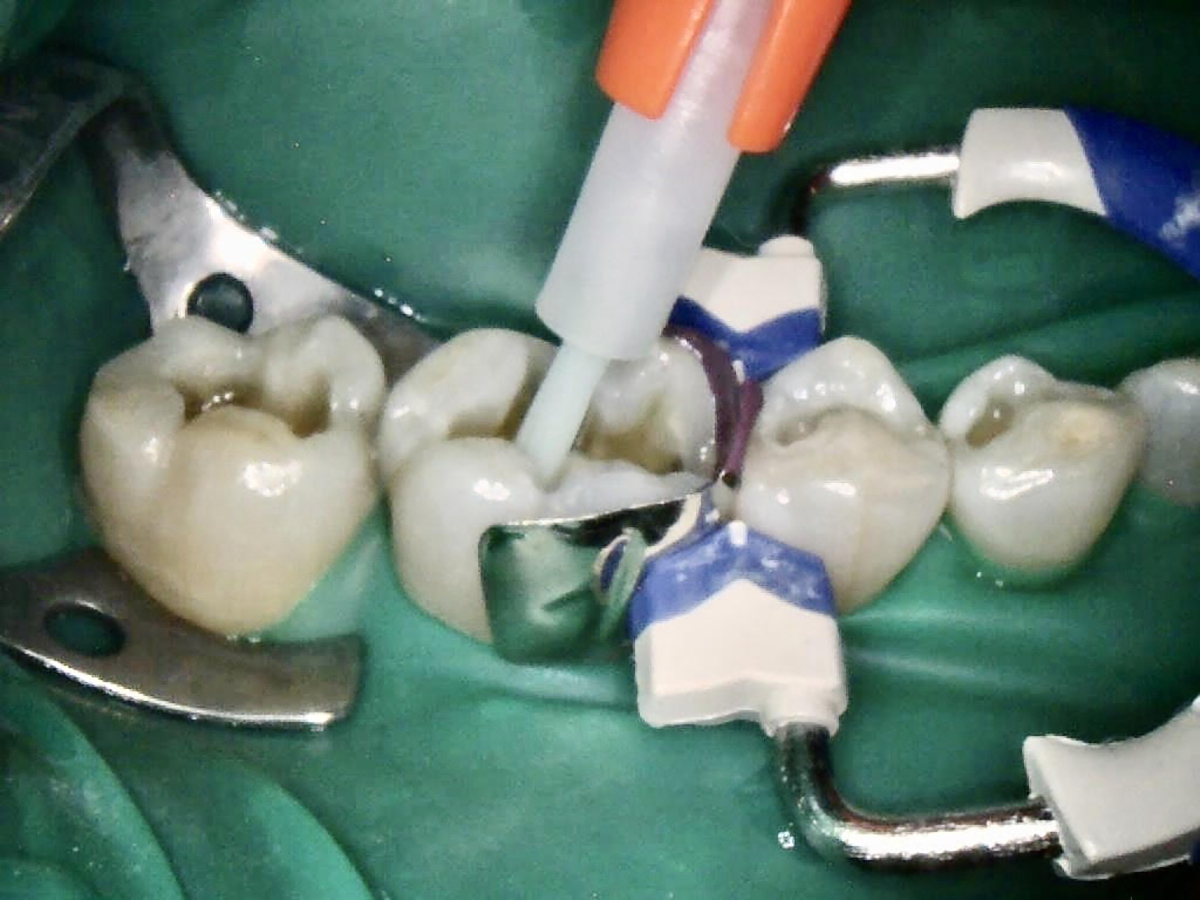

Fig 3. Selective enamel etching on tooth.

Figure 3

After a clean and neat cavity preparation, liner was placed on the deep cavity surface to mask the dark amalgam stain. The liner was light-cured for 20 seconds. A wide bevel was placed on the occlusal surface, and then a ring and matrix were placed. A selective enamel etching was performed with 37% phosphoric acid (Figure 3), rinsed, and dried. Universal bond was prepared by adding one drop from each bottle of the adhesive product into a mixing well and then briefly mixing. The bond was then placed (Figure 4) and air-dried with low air for 5 seconds, then with stronger air for another 5 seconds. No light-curing was needed for this bonding system. Then, one-shade composite was placed in small increments using a condenser. Before light-curing, some occlusal anatomy was created using hand instruments, including an acorn-shaped burnisher (Figure 5) and blue titanium CIB3. The occlusal adjustments and more detailed anatomy were created using a football-shaped diamond bur and a needle-shaped diamond bur. The final finishing and polishing were done using a large, coarse disc, a fine-needle diamond bur, and white Arkansas stone. A postoperative photograph (Figure 6) showed how the restoration blended naturally with the tooth. Figure 7 and Figure 8 feature a bitewing x-ray and photograph of the tooth taken during the 6-month recall examination.